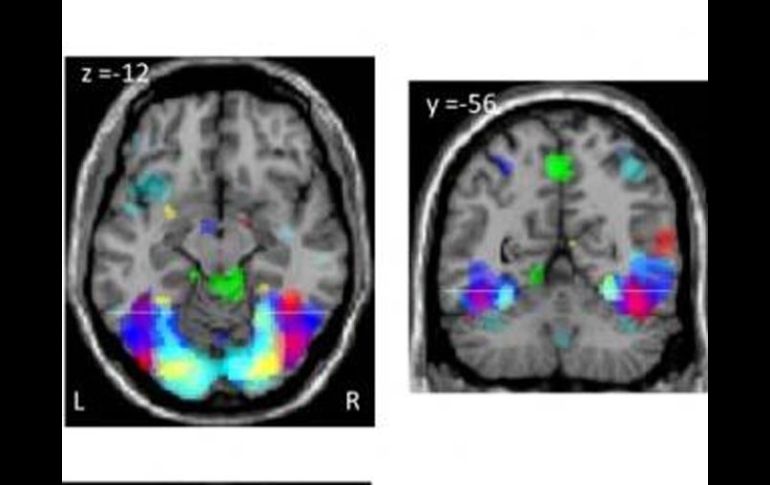

Tecnología | Unos experimentos muestran la modulación de la actividad mental Aprender a leer y escribir deja huella en el cerebro Unos experimentos muestran la modulación de la actividad mental en personas analfabetas y alfabetizadas Por: EL INFORMADOR 14 de noviembre de 2010 - 19:36 hs Las zonas del cerebro especializadas en el vocabulario y en el reconocimiento visual, funcionan también en la alfabetizació. ELPAIS.COM / PARIS, FRANCIA (14/NOV/2010).-La alfabetización, la capacidad de leer y escribir, es algo muy reciente en la historia del ser humano, por lo que el cerebro debió recurrir a lo que ya tenía para hacer frente a esta nueva e importante actividad mental y no habría desarrollado mecanismos nuevos, genéticos o de desarrollo, algo que exige bastante tiempo evolutivo, creen los científicos. Unos investigadores han hecho ahora unos experimentos curiosos para medir su huella en el cerebro, analizando con técnicas de resonancia funcional el cerebro de 63 voluntarios brasileños y portugueses: 11 analfabetos, 22 alfabetizados ya de adultos y 31 que aprendieron a leer y escribir de niños. Han identificado así las regiones cerebrales moduladas en la alfabetización, que están en zonas ya conocidas por su especialización en el vocabulario y en el reconocimiento visual de caras. Además la alfabetización mejora las funciones del habla. Todavía no saben si estos cambios en la anatomía cerebral, esta especialización dedicada a leer y escribir, merman o no la capacidad, por ejemplo, de reconocer rostros. Stanislas Dehaene (Universidad Paris-Sur) y sus colegas destacan en el informe de su investigación en la revista Science que no sólo se aprecian diferencias en el cerebro entre las personas analfabetas y alfabetizadas, sino que son notables también las diferencias en aquellos que aprendieron de adultos, lo que indica que la educación a edades tardías "puede refinar profundamente la organización de la corteza". El experimento es interesante, además, porque parte de los sometidos a resonancia funcional son analfabetos, mientras que la inmensa mayoría de los sujetos sanos de ensayos de este tipo son voluntarios de entornos académicos. Durante las pruebas, los científicos presentaron a las 63 personas diferentes tareas de reconocimiento de rostros, problemas de cálculo y respuesta a frases oídas y leídas. La alfabetización, ya sea adquirida en la infancia o en la edad adulta, refuerza la respuesta cerebral de varias maneras, explican Dehaene y sus colegas. Por un lado relanza la organización de la corteza visual, pero también permite que, en respuesta a frases escritas, se active toda la red del lenguaje hablado en el hemisferio izquierdo. "La capacidad de leer, una invención cultural tardía, se aproxima a la eficiencia de la vía de comunicación más evolucionada de la especie humana, que es el habla", explican en Science. Temas Ciencia Cerebro Lee También Julieta Fierro será homenajeada en la FIL Nobel de Química premia el desarrollo de estructuras metal-orgánicas Nobel de Física para Clarke, Devoret y Martinis por descubrimiento sobre fenómenos cuánticos Nobel de Medicina premia investigación sobre el control del sistema inmunitario Recibe las últimas noticias en tu e-mail Todo lo que necesitas saber para comenzar tu día Registrarse implica aceptar los Términos y Condiciones